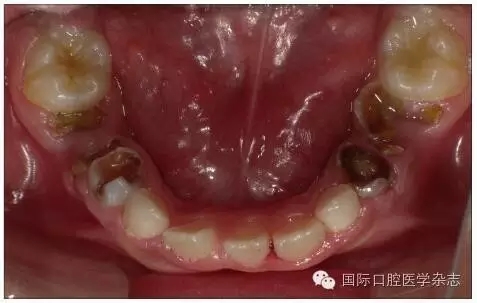

個(gè)別牙先天缺失常常造成牙列異常間隙,多數(shù)牙先天缺失會(huì)影響咀嚼功能和牙列形態(tài),嚴(yán)重者影響面容和美觀。牙齒的形態(tài)異常,如融合牙等會(huì)使牙弓大小、形態(tài)及咬合關(guān)系發(fā)生異常。乳牙滯留是指繼承恒牙已經(jīng)萌出,未能按時(shí)脫落的乳牙。乳牙牙根未吸收或非典型性吸收可導(dǎo)致恒牙萌出方向改變、位置異常,常見于下頜乳中切牙滯留,恒中切牙于舌側(cè)出齦,呈現(xiàn)“雙排牙”現(xiàn)象(圖5)。上頜牙齒在滯留乳牙腭側(cè)出齦則可能形成反(圖6)。

圖6 右上乳中切牙遲脫引起右上中切牙腭向異位萌出

Fig 6 Late exfoliation ofright upper primary incisor caused ectopicpalatal eruption of right upper incisor